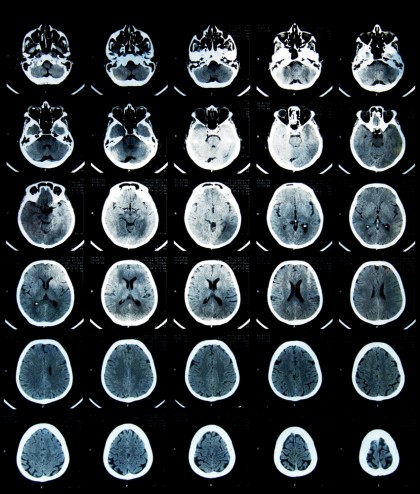

Cercetătorii au realizat scanări RMN la 59 de adolescenți obezi și 61 adolescenți sănătoși, vizând în special materia albă din creier, zona în care se află țesutul neurologic conector - supranumit „autostrada” dintre regiunile creierului.

Rezultatele scanărilor au evidențiat la adolescenții obezi leziuni în corpus callosum și scăderea materiei albe în girusul orbitofrontal - regiune legată de controlul emoțional și circuitul de recompensare. Aceste modificări au fost puse pe seama inflamației.

Potrivit cercetătotilor, modificările din creier se regăsesc în regiunile responsabile pentru controlul apetitului, emoțiilor și funcțiilor cognitive. Totodată, scanările au evidențiat o corelație pozitivă între schimbările pe care obezitatea le produce în creier și hormoni ca leptina și insulina.

Nu este pentru prima oară când cercetătorii stabilesc o legătură între obezitate și sănătatea creierului: un studiu din 2016 a descoperit că la adulții de vârstă mijlocie obezi materia albă părea cu 10 ani mai îmbătrânită față de adulții normoponderali.